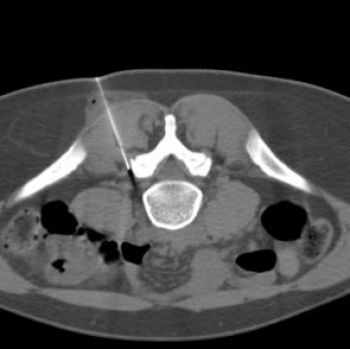

Il s’agit d’un geste habituel et fréquent, non douloureux ; vous serez installés à plat ventre, des images scanner de repérage sont faites, l’infiltration est faite doucement en certifiant le bon positionnement grâce aux images scanner .

l’ensemble de l’examen dure environ 20 mn.